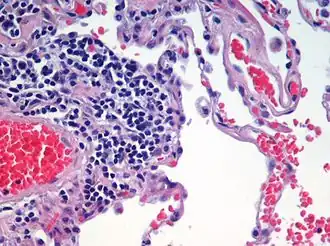

Automated tissue image analysis or histopathology image analysis (HIMA) is a process by which computer-controlled automatic test equipment is used to evaluate tissue samples, using computations to derive quantitative measurements from an image to avoid subjective errors.

In a typical application, automated tissue image analysis could be used to measure the aggregate activity of cancer cells in a biopsy of a cancerous tumor taken from a patient. In breast cancer patients, for example, automated tissue image analysis may be used to test for high levels of proteins known to be present in more aggressive forms of breast cancers.

Specimen preparation is critical for evaluating the tumor in the automated system. In the first part of the preparation process the biopsied tissue is cut to an appropriate size (typically 4 mm), fixed in buffered formalin, dehydrated in ethanol-xylene, embedded in paraffin, thin sectioned typically to 4 um slices, then mounted onto at least two barcoded slides (a control and a test). Next the paraffin is removed from the tissue, the tissue is rehydrated, then stained. Any inconsistency in these procedures from case to case may result in uncertainties in the outcome of the analysis. These potential and irreducible inconsistencies in analysis results motivated the development of Automated Tissue Image Systems.

Image analysis involves complex computer algorithms which identify and characterize cellular color, shape, and quantity of the tissue sample using image pattern recognition technology based on vector quantization. Vector representations of objects in the image, as opposed to bitmap representations, have superior zoom-in ability. Once the sample image has been acquired and resident in the computer's random access memory as a large array of 0's and 1's, a programmer knowledgeable in cellular architecture can develop deterministic algorithms applied to the entire memory space to detect cell patterns from previously defined cellular structures and formations known to be significant.[9]